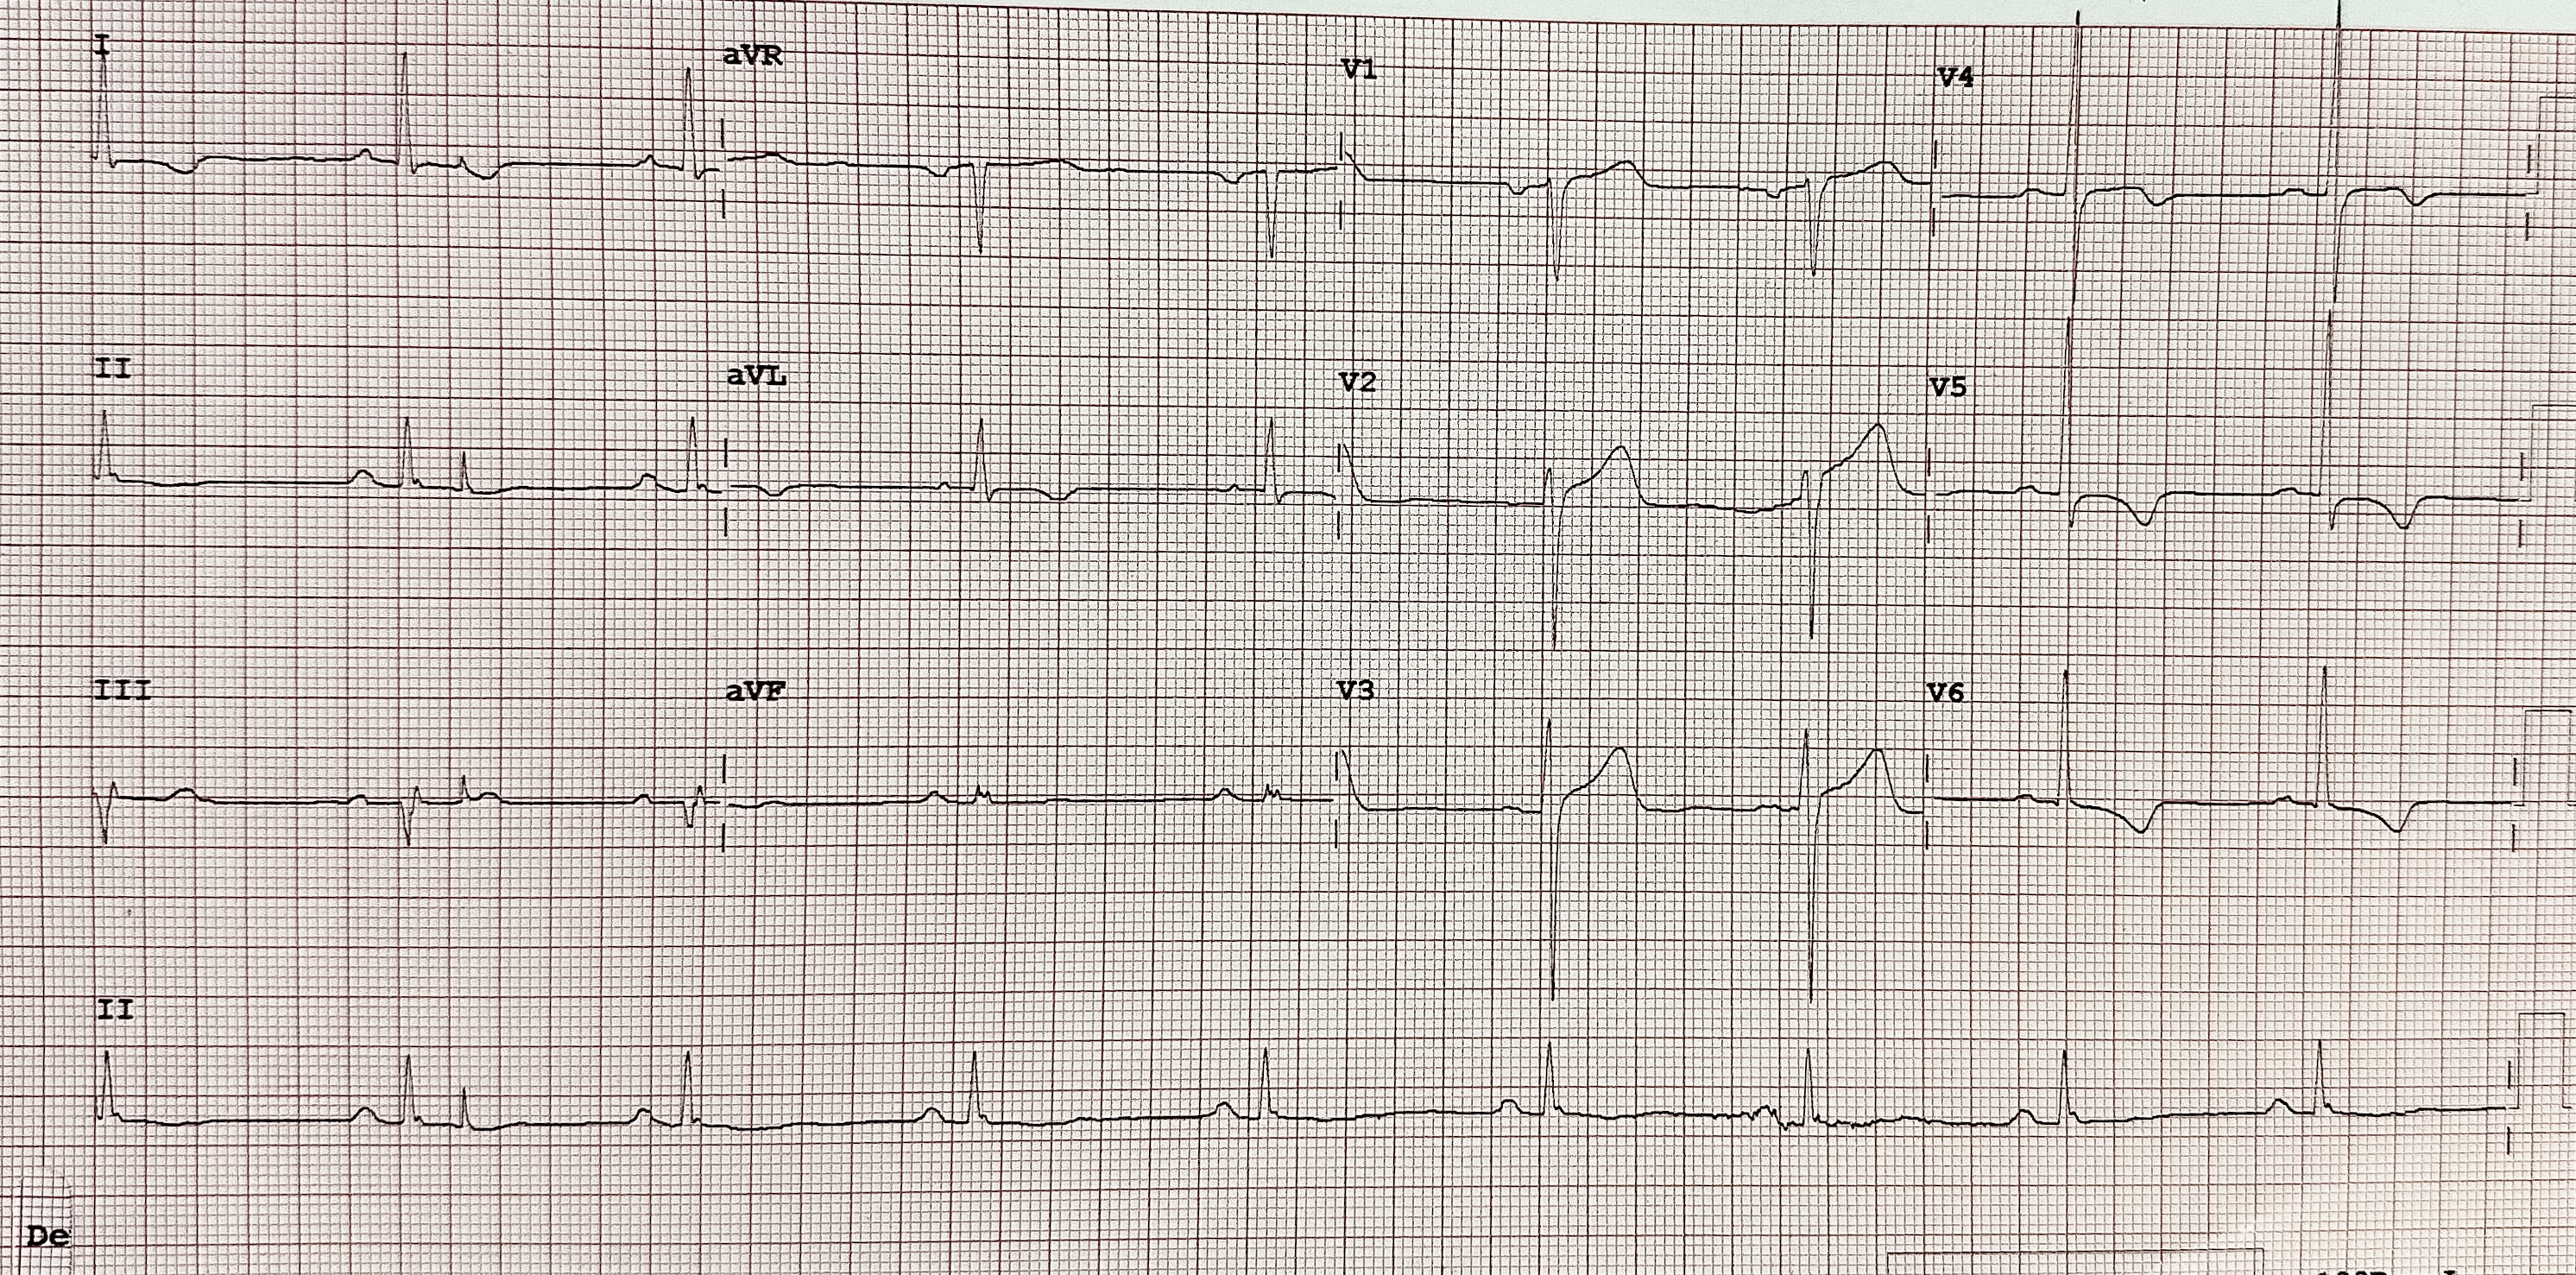

A 76-year-old male presented with worsening angina over the past year. He had multivessel coronary artery disease (CAD) with a prior percutaneous coronary intervention (PCI) in 2004, severe aortic stenosis (AS), and multiple comorbidities, including diabetes mellitus, hypertension, and chronic obstructive pulmonary disease (COPD) and chronic kidney failure (eGFR 46 mL/min/1.73m²). Physical examination revealed an ejection systolic murmur. ECG revealed left ventricular hypertrophy.